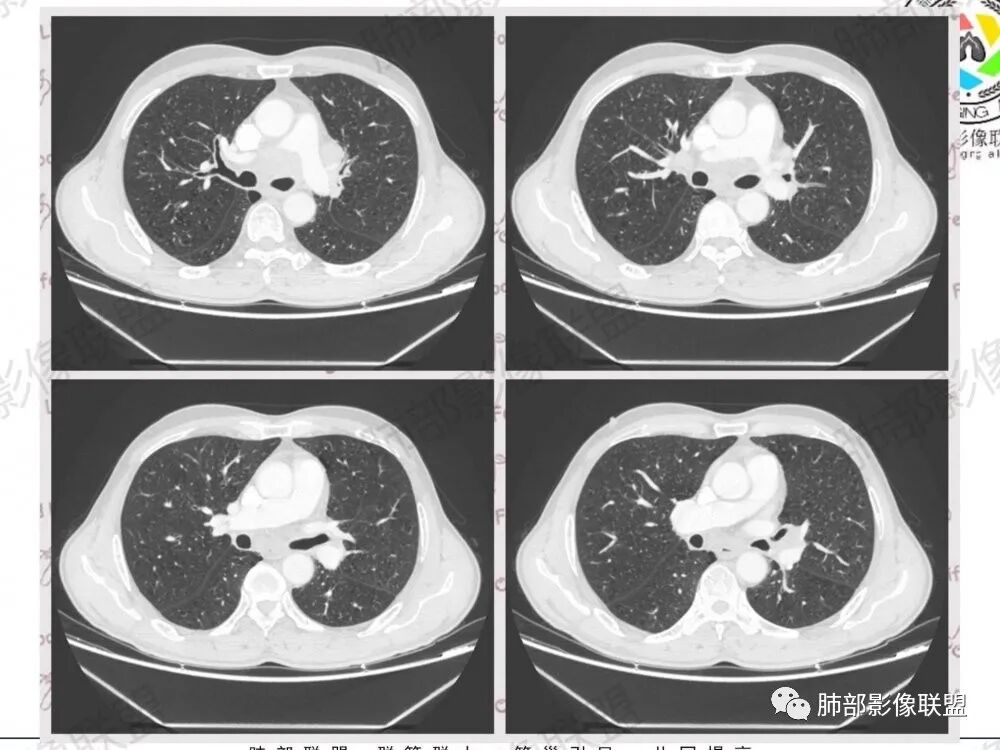

57岁男性,长期吸烟史,有血吸虫病史,有粉尘接触史。发现纵隔淋巴结肿大2年,声嘶伴咳嗽咳痰半月。两年前胸部CT见左上肺尖后段结节并肺门淋巴结肿大,治疗后左上肺结节消失。目前胸部CT:肺气肿,左上肺尖后段见条索影(原来结节治疗后的改变?),肺门、纵隔淋巴结肿大并融合,似见薄壁包膜样强化。考虑淋巴结结核可能性大,注意鉴别淋巴瘤、转移、结节病等。

男性,57岁,发现纵膈淋巴结肿大,现声嘶伴咳嗽咳痰。COPD背景,纵隔内、左肺门多发肿大淋巴结相互融合,冰冻纵隔?增强后轻度强化,主气管向右侧推移。考虑肺癌,小。

左上肺门和左下肺门淋巴结,纵膈淋巴结肿大,融合明显。右肺门未见肿大淋巴结。上腔和邻近左上,下肺动脉推移受侵变细明显。先考虑恶性肿瘤的淋巴结转移。病理亚型不敢定了,前两天刚碰见一个这样的腺,先猜小细胞。既往结核粉尘吸入,淋巴瘤第二位吧。

中老年男性,长期吸烟,肺气肿明显,发现纵隔淋巴结两年了,声音嘶哑,病灶压迫喉返神经了?喉部有占位吗?左肺尖小片状病灶,周围多发长条纤维牵拉,胸膜增厚,纵隔及左肺门多发肿大淋巴结,增强后显示淋巴结融合且坏死明显,薄环状强化。如果是恶性肿瘤,小细胞癌或者鳞癌,肺内病变应该增大增多了;一元化我考虑纵隔淋巴结结核,左肺尖结核灶。

1.左肺门及纵隔见异常增大淋巴结,部分融合,不均匀轻度强化,未见明显坏死。

肿大淋巴结与纵隔血管等结构“无缝”贴合。

2.纵隔增宽但依旧居中。

1、小细胞癌(SCLC)自内胚层未成熟细胞发生,具有上皮细胞和神经内分泌细胞双重性质;小细胞癌基本上产生充实性胞巢,无腺管形成,缺乏间质反应,无腺癌纤维化的收缩性。

2、小细胞癌恶性程度高,发展迅速,转移发生早;常有纵隔淋巴结的明显增大融合(发生率达96.5%),呈“冰冻纵隔”,淋巴转移常为逐站的连续性转移;亦有血行转移,脑、肾上腺、肝、胰、骨髓等;转移灶常比原发灶大得多,即“娘小崽大”特点;

3、因其对血管、支气管破坏程度轻,故坏死相对较轻,极少出现空洞;小细胞肺癌支气管壁肥厚、管腔狭窄,但表面可有正常黏膜,除非狭窄非常严重,否则不会引起支气管刺激症状,故该症状对其早期诊断无意义;受累支气管末梢侧阻塞性炎症少。